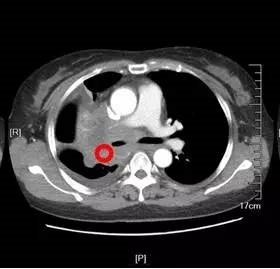

实验室检查应包括:全血细胞计数和分类计数以及红细胞沉降率;血清生化指标,包括电解质、肝肾功能、白蛋白和乳酸脱氢酶;可使用影像学检查指导活检和评估可疑的器官受累。

需通过组织活检来诊断经典型霍奇金淋巴瘤及明确组织亚型。一般首选外周淋巴结的切除活检,但多点针芯穿刺活检可能就已足够。然而,细针抽吸活检一般无法提供充足的组织进行所有必需的检查,且不能得到明确的组织学分类。